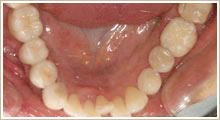

一切金属を使わずに修復。

▼治療前

▼治療後